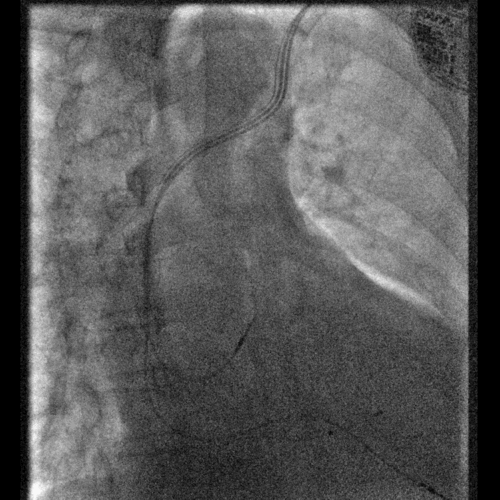

右室右房电极的植入

最终植入美敦力 Viva CRTP

程控出参数良好,目前以Adaptiv Biv的模式起搏,期待后续疗效